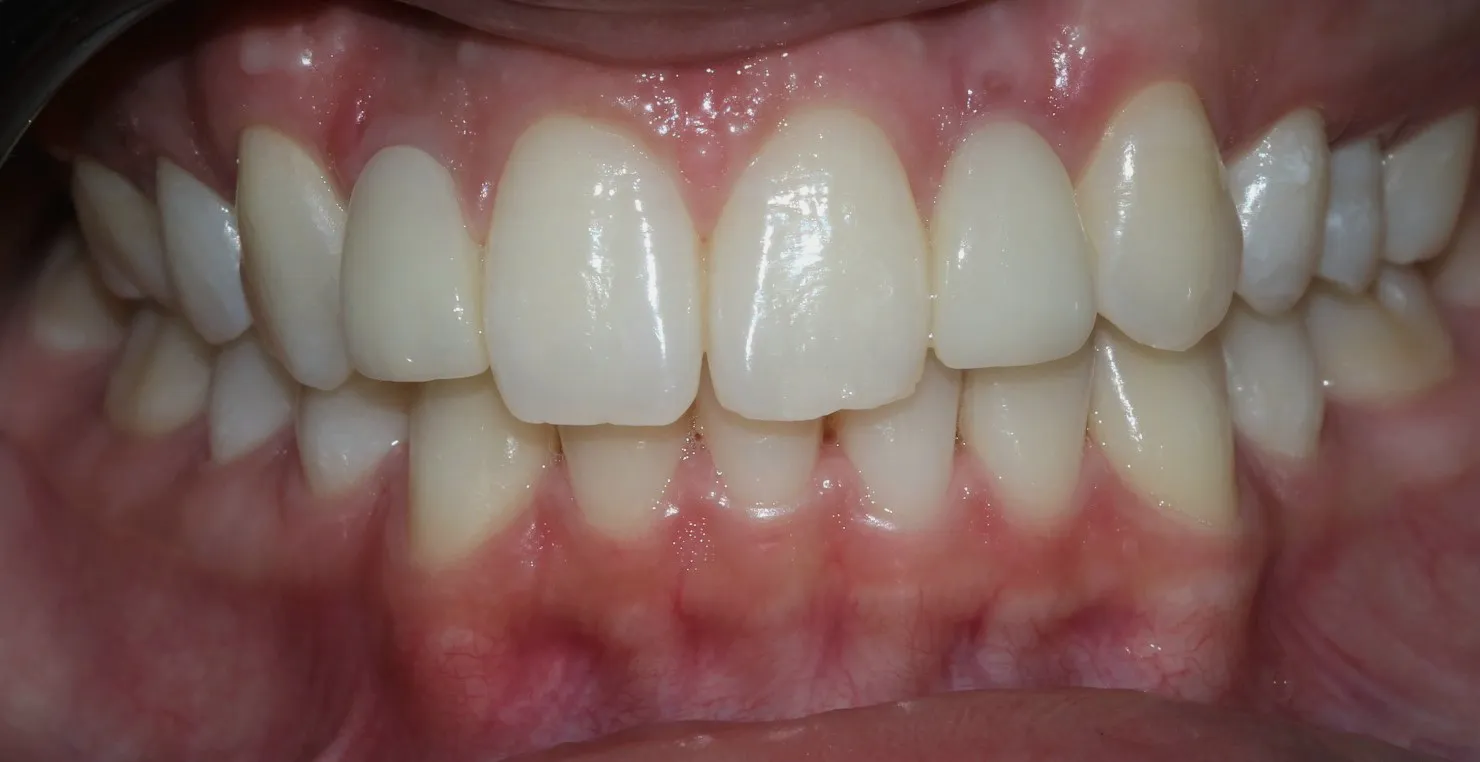

Caso 3

Se realizan 6 carillas dentales en Emax, mejorando frente estético, y funcion masticatoria.